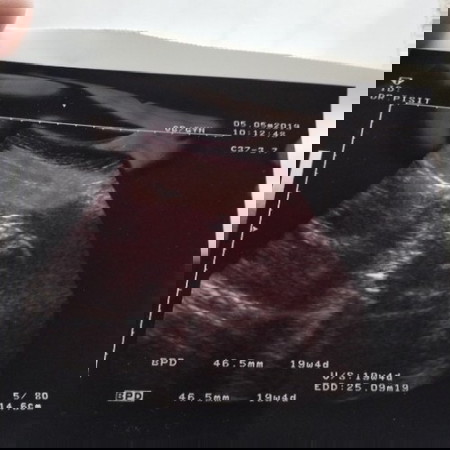

มีใครดูภาพอันตร้าซาวด์เป็นบ้างค่ะเราพึ่งไปซาวมาวันอาทิตย์ที่5คุณหมอบอกว่าได้ลูกผู้หญิงตอนนี้เราอายุครรภ์ได่5เดือนค่ะ

ดูไม่ออกเลยค่ะ คุณหมอคงอาศัยความเชี่ยวชาญ แต่เดี๋ยวคงจะเห็นชัดขึ้น